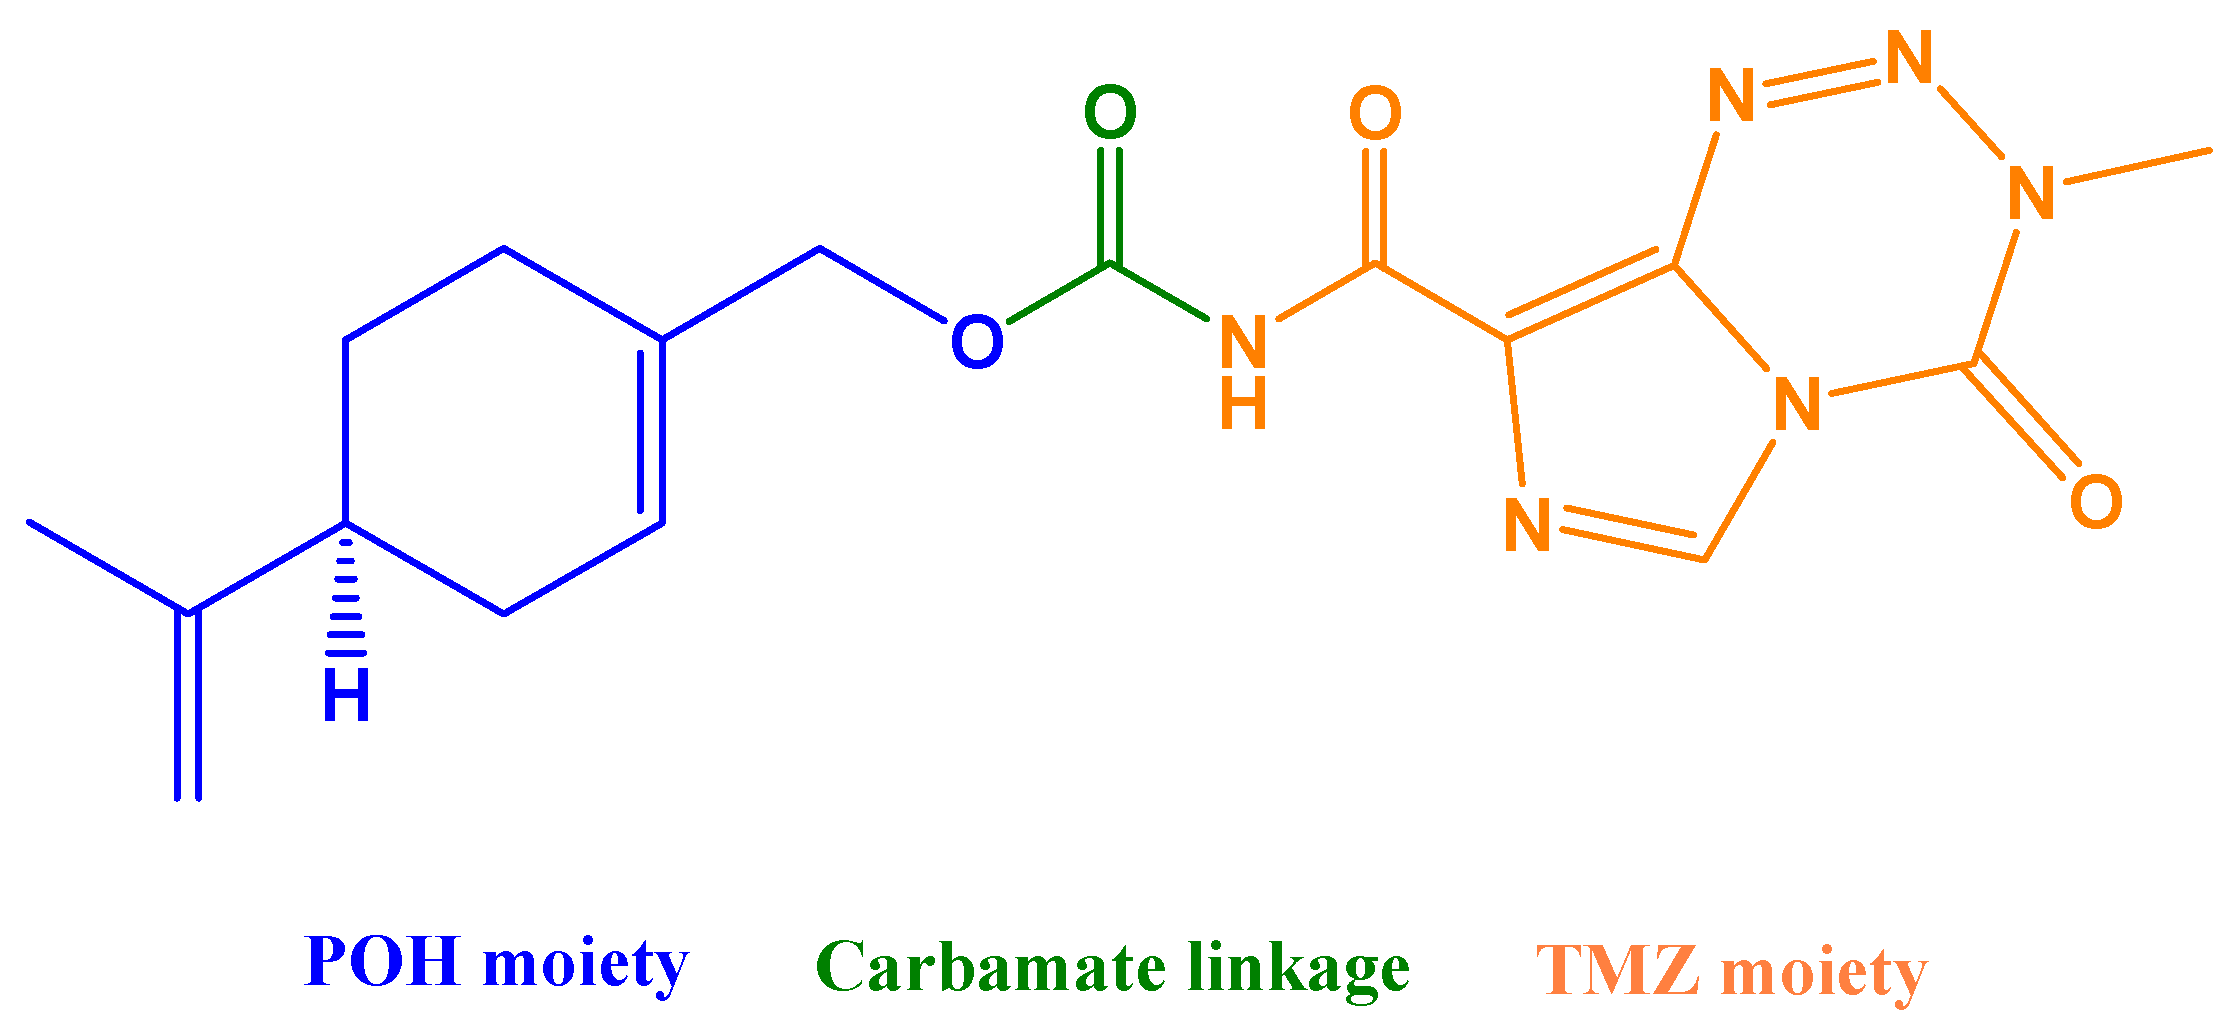

6.1.1. POH Conjugated to Temozolomide (NEO212)

- Chen, T.C.; Cho, H.-Y.; Wang, W.; Barath, M.; Sharma, N.; Hofman, F.M.; Schönthal, A.H. A Novel Temozolomide–Perillyl Alcohol Conjugate Exhibits Superior Activity against Breast Cancer Cells In Vitro and Intracranial Triple-Negative Tumor Growth In Vivo. Mol. Cancer Ther. 2014, 13, 1181–1193. [Google Scholar] [CrossRef] [PubMed] [Green Version]

- Chen, T.C.; Cho, H.-Y.; Wang, W.; Wetzel, S.J.; Singh, A.; Nguyen, J.; Hofman, F.M.; Schönthal, A.H. Chemotherapeutic effect of a novel temozolomide analog on nasopharyngeal carcinoma in vitro and in vivo. J. Biomed. Sci. 2015, 22, 71–80. [Google Scholar] [CrossRef] [PubMed] [Green Version]

- Schönthal, A.; Swenson, S.; Minea, R.; Kim, H.; Cho, H.; Mohseni, N.; Kim, Y.-M.; Chen, T. Potentially Curative Therapeutic Activity of NEO212, a Perillyl Alcohol-Temozolomide Conjugate, in Preclinical Cytarabine-Resistant Models of Acute Myeloid Leukemia. Cancers 2021, 13, 3385. [Google Scholar] [CrossRef] [PubMed]

- Chen, T.C.; Cho, H.-Y.; Wang, W.; Nguyen, J.; Jhaveri, N.; Rosenstein-Sisson, R.; Hofman, F.M.; Schönthal, A.H. A novel temozolomide analog, NEO212, with enhanced activity against MGMT-positive melanoma in vitro and in vivo. Cancer Lett. 2015, 358, 144–151. [Google Scholar] [CrossRef] [PubMed]

- Cho, H.-Y.; Swenson, S.; Thein, T.Z.; Wang, W.; Wijeratne, N.R.; I Marín-Ramos, N.; E Katz, J.; Hofman, F.M.; Schönthal, A.H.; Chen, T.C. Pharmacokinetic properties of the temozolomide perillyl alcohol conjugate (NEO212) in mice. Neuro-Oncol. Adv. 2020, 2, vdaa160. [Google Scholar] [CrossRef] [PubMed]

- Cho, H.-Y.; Wang, W.; Jhaveri, N.; Lee, D.J.; Sharma, N.; Dubeau, L.; Schönthal, A.H.; Hofman, F.M.; Chen, T.C. NEO212, Temozolomide Conjugated to Perillyl Alcohol, Is a Novel Drug for Effective Treatment of a Broad Range of Temozolomide-Resistant Gliomas. Mol. Cancer Ther. 2014, 13, 2004–2017. [Google Scholar] [CrossRef] [PubMed] [Green Version]

- Jhaveri, N.; Agasse, F.; Armstrong, D.; Peng, L.; Commins, D.; Wang, W.; Rosenstein-Sisson, R.; Vaikari, V.P.; Santiago, S.V.; Santos, T.; et al. A novel drug conjugate, NEO212, targeting proneural and mesenchymal subtypes of patient-derived glioma cancer stem cells. Cancer Lett. 2016, 371, 240–250. [Google Scholar] [CrossRef] [PubMed]